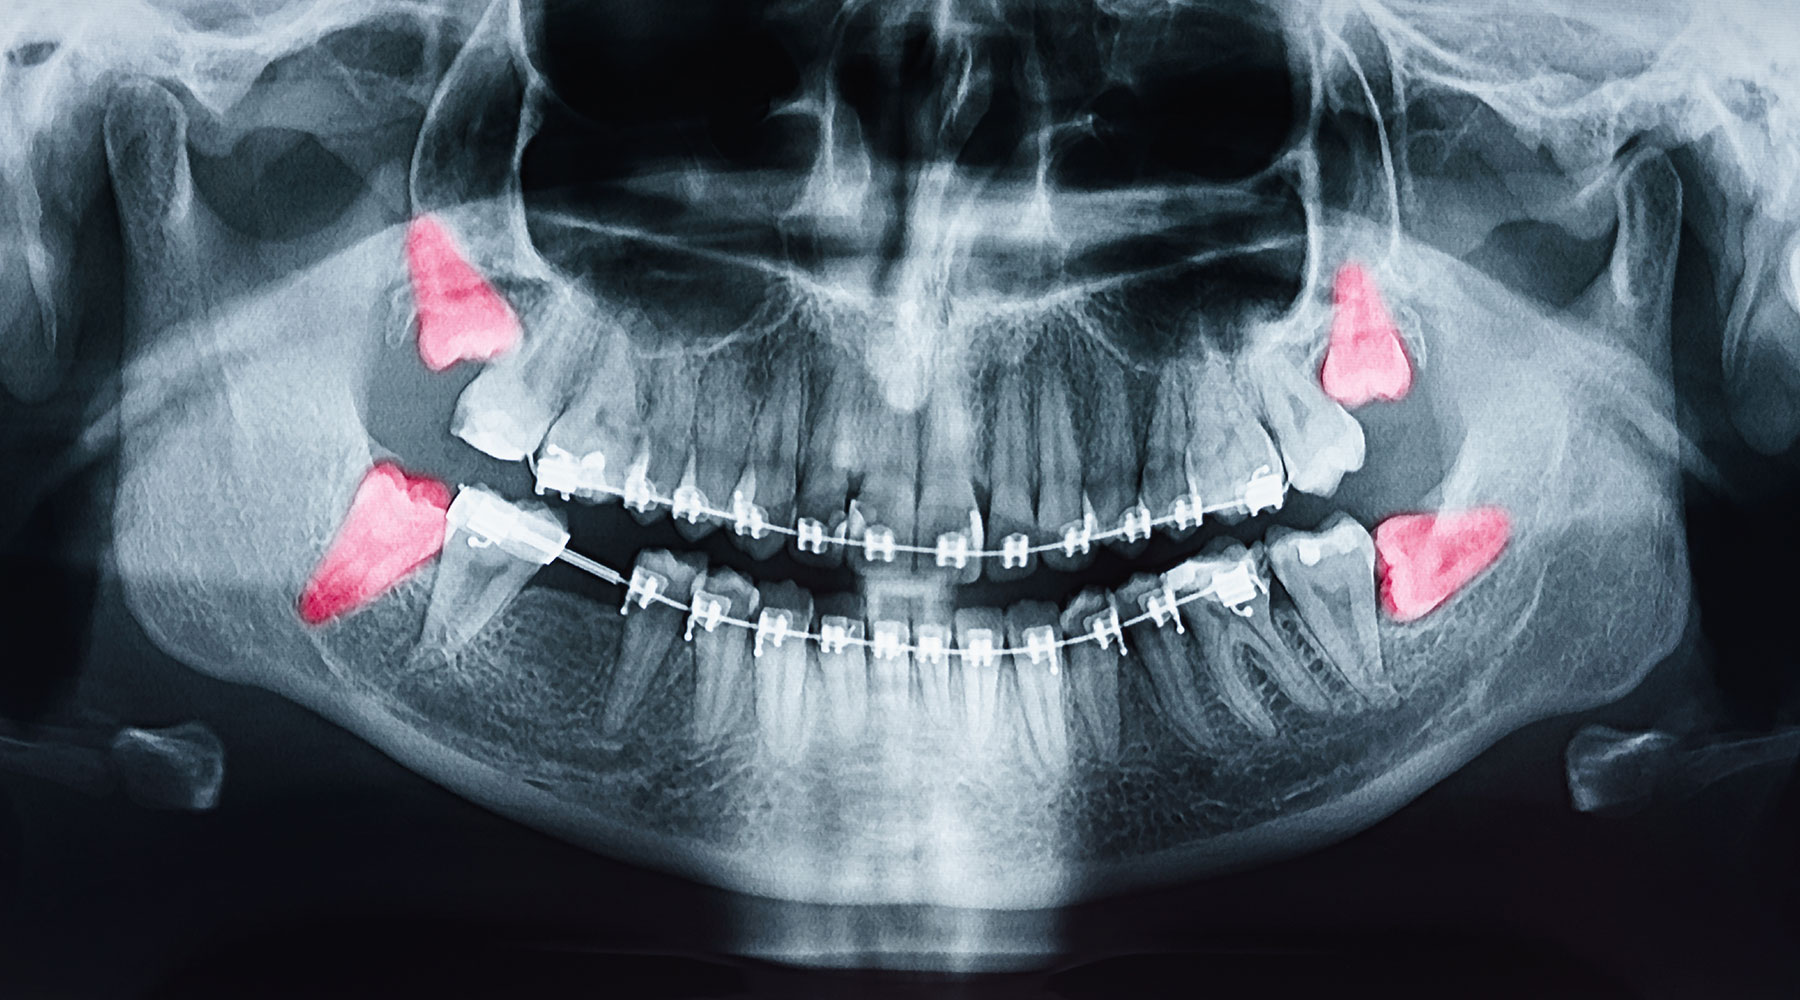

hallo, die Frage richtet sich ausschließlich an Personen, die bei Ihrer OP der Nerv geschädigt wurde bzw die nach der OP für eine lange Zeit im Kinn, Lippen und Zungenbereich taub waren Nur in selten Fällen bleibt eine dauerhafte Nervenschädigung lingualis im Rahmen einer Weisheitszahnextraktion wird eine chirurgische Exploration über die vorbestehende Operationsnarbe vorgenommen und eine Erweiterung des Zugangs nach anterior vorgenommen